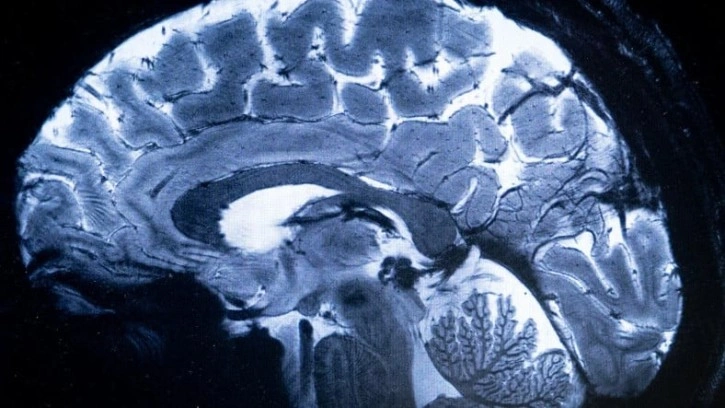

Fransa'da Atom Enerjisi Komisyonu (CEA) tarafından geliştirilen dünyanın en güçlü MRI tarama cihazı, tarihinde ilk defa insan beyninin görüntülenmesi için kullanıldı. Aslında 2021 yılında hizmete alınan cihazın insanlar üzerinde kullanılabilmesi için gerekli izin ve onaylar üç yılda ancak tamamlanabildi.

Projede yer alan isimlerden Fizikçi Alexandre Vignaud, "Daha önce CEA'da böyle bir isabet görmemiştik." ifadelerini kullanırken, standart bir MRI görüntüsü ile cihazdan gelen görüntüleri de karşılaştırdı. Vignaud, yeni chaz ile daha önce görüntülenemeyen ya da çok az görüntülenebilen, beynin farklı bölgelerindeki ince kılcal damarları bile çok net şekilde gözlemleyebildiklerini söyledi.

Manyetik alanların ölçü birimi olarak Tesla adında bir ölçü birimi kullanılıyor. Standart hastane MRI cihazları genellikle 10 Tesla veya altında manyetik alanlar oluştururken yeni cihaz ise 11,7 Tesla gücünde manyetik alan oluşturabiliyor. Bu da daha detaylı incelemeleri mümkün kılıyor. Yeni makine 10 kat daha yüksek görüntüleme kapasitesine sahip. 5 metre çapındaki tarayıcıda 132 tonluk bir mıknatıs bulunuyor.